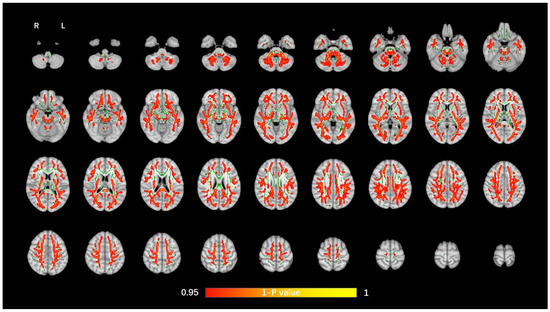

The average FA WM skeleton of all subjects was constructed in TBSS analyses, as shown by the green line in Figure 1, Figure 2, Figure 3 and Figure 4. An analysis of variance of voxel level was carried out on the WM skeleton, and the differences among the three groups were compared. p < 0.05 after FWE correction based on TFCE was statistically significant. Statistically significant areas were expanded to better show the position of WM fiber bundles, as shown in the red part in Figure 1, Figure 2, Figure 3 and Figure 4. The statistical results showed that the DTI indexes of most fiber bundles were statistically significant. There was a significant statistical difference in the FA, MD, AD, and RD values of the FMI, FMA, IFOF, SLF, ILF, ATR and corticospinal tract (CCT) among the three groups (p < 0.05; Figure 1, Figure 2, Figure 3 and Figure 4).

Figure 1.

Voxel-wise TBSS analysis results of FA images among the WML-VCIND, WML-VaD, and HC groups. Green represents the mean WM skeleton of all subjects. Red-yellow (thickened for better visibility) represents regions with a significant F-test statistical difference (p < 0.05, TFCE-based FWE-corrected). TBSS, tract-based spatial statistics; FA, fractional anisotropy; HC, healthy controls; WML, white matter lesions; WML-VCIND, WML and non-dementia vascular cognitive impairment; WML-VaD, WML and vascular dementia.